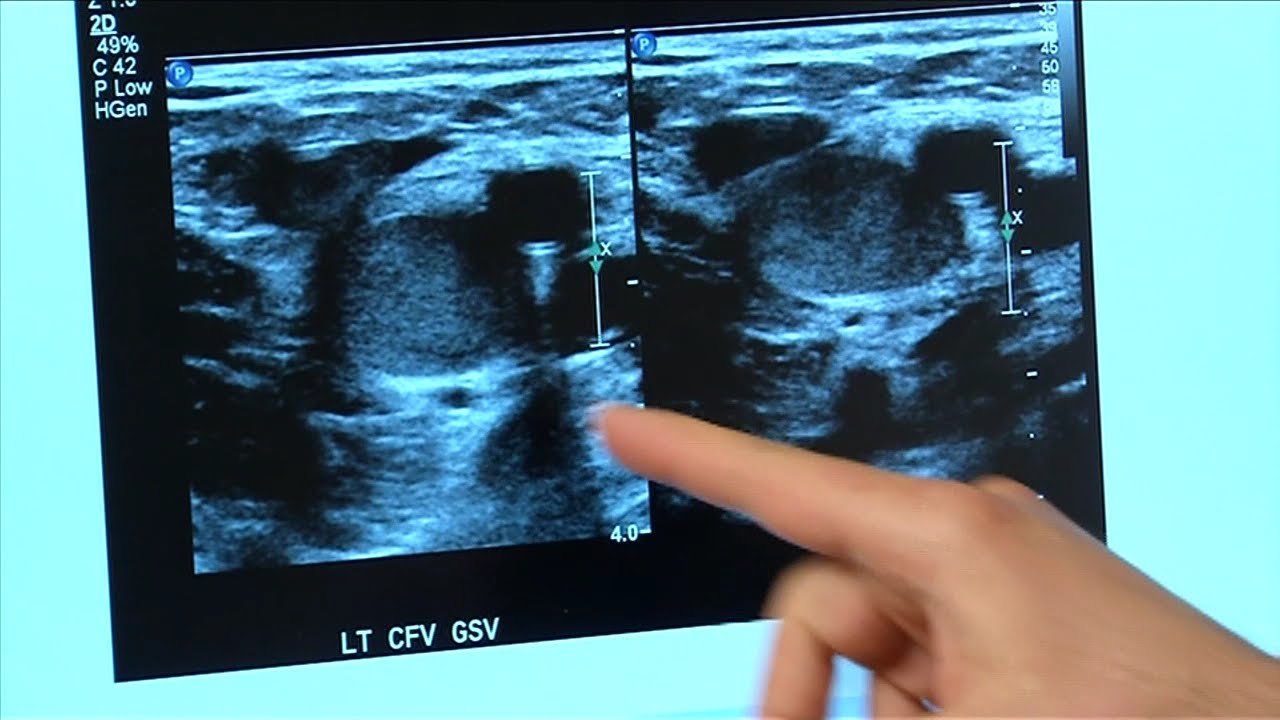

Patients with pre-existing conditions, such as heart disease and diabetes, are more at risk for complications because of coronavirus. But Dr. Becker said research is showing some otherwise healthy patients have contracted deep vein thrombosis, more commonly known as blood clots and pulmonary embolism. A pulmonary embolism is a blood clot that develops in the leg and travels up the leg to the lungs. Pulmonary embolisms can be fatal.

“We and others have seen young and otherwise healthy individuals with COVID-19, and some of them have been asymptomatic, who have experienced strokes, deep vein thrombosis — that is a blood clot in the legs — and pulmonary embolism.”

Oddly enough, Dr. Becker said with COVID-19, some blood clots are actually developing in the lungs rather than traveling through the leg to the lungs.